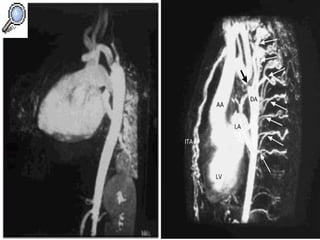

Cateterismo cardiaco: En casos atípicos o con lesiones asociadas El aortograma se realiza en proyección OIA Un gradiente de  40mmHg   ó más es significativo Determina circulación colateral

Cateterismo cardiaco: Encasos atípicos o con lesiones asociadas El aortograma se realiza en proyección OIA Un gradiente de 40mmHg ó más es significativo Determina circulación colateral